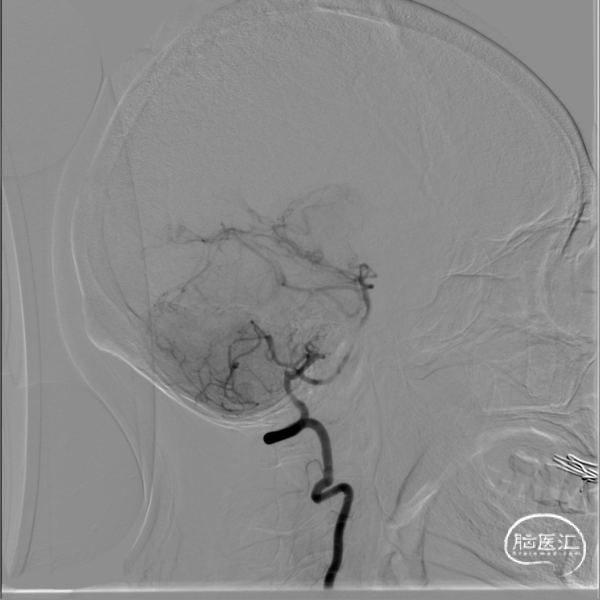

3、椎基底动脉系统:

右侧椎动脉优势型。

左侧椎动脉血管纤细,远端可见基底动脉浅淡显影。

右侧椎动脉优势型,远端汇入基底动脉。

基底动脉中段重度狭窄,狭窄率约80%,双侧大脑后动脉可见显影。

术前DSA影像: